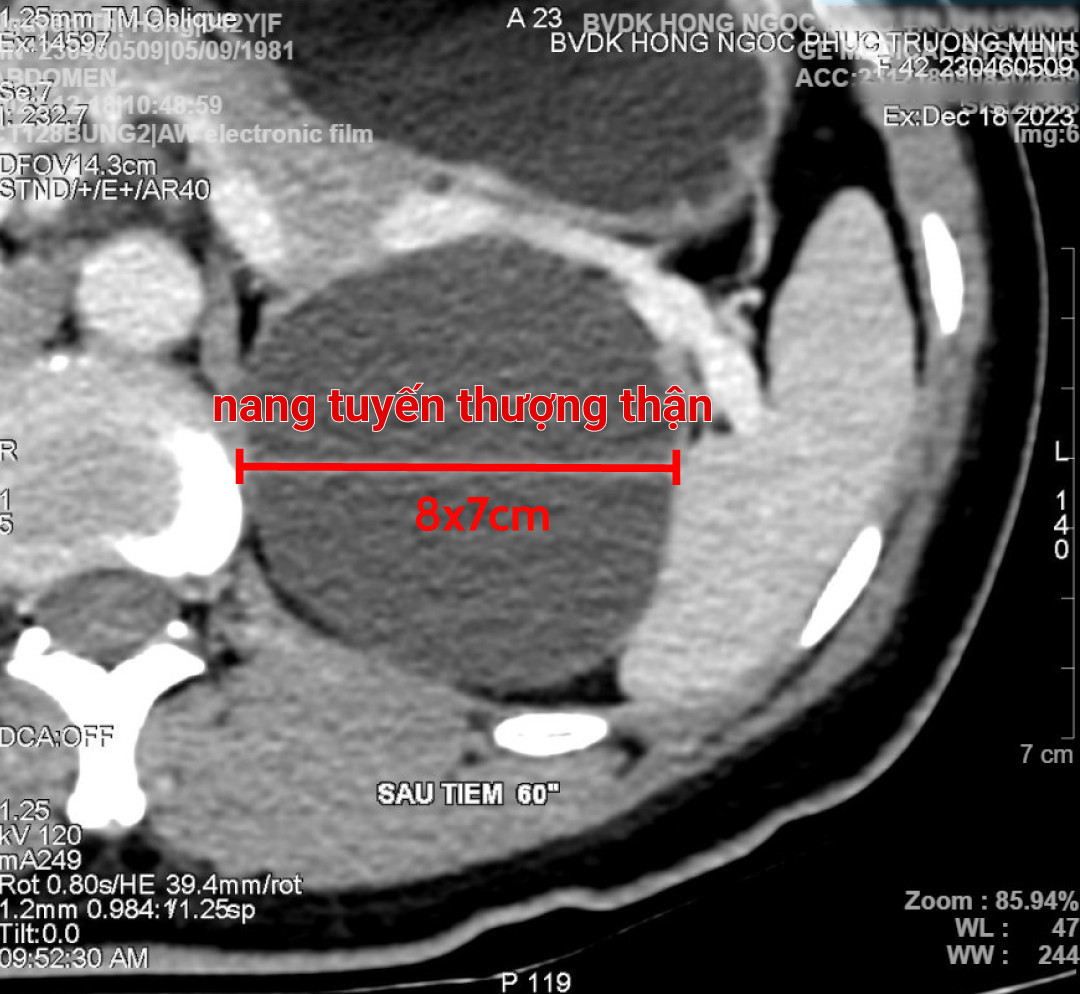

Bệnh nhân P.T.H đến bệnh viện Đa khoa Hồng Ngọc trong tình trạng đau bụng. Kết quả CT và chụp siêu âm ổ bụng phát hiện một cấu trúc dạng nang kích thước lớn 8x7cm, nằm ở vị trí cực trên thận trái, bắt đầu có các nốt vôi hóa ở thành nang. Sau hội chẩn, các bác sĩ xác định đây là nang tuyến thượng thận và có chỉ định mổ bóc nang.

| Kết quả chụp CT cho thấy chị H. có một cấu trúc nang có kích thước lớn 8x7 cm |